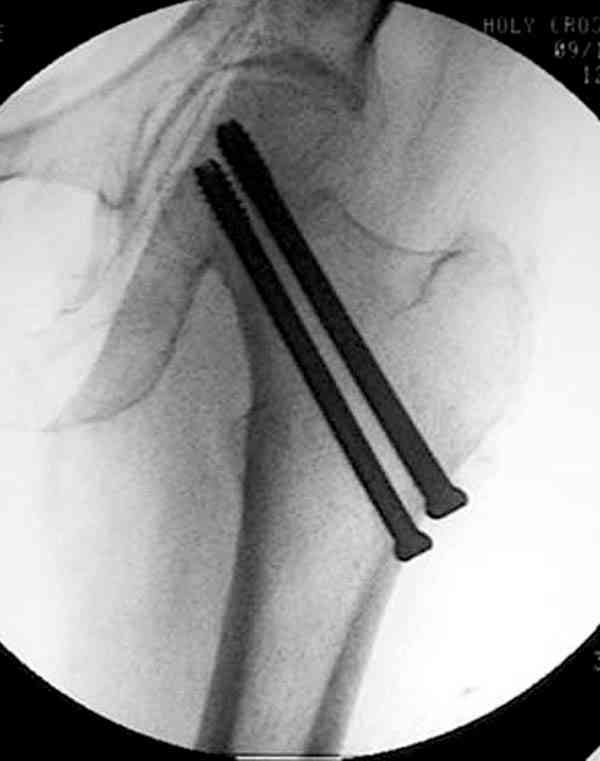

Коллега Челноков прав, здесь еще имеется риск перелома за счет ослабления латерального кортекса. Во время установки канюлированных шурупов за редким исключением спица вводится с одного раза, множественные попытки ослабляют латеральный кортекс, что станет источником перелома в этом месте.

Здесь случай перелома из-за ослабления латерального кортекса через 3 недели после операции на шейке. Шурупы были установлены под большим углом, слабый латеральный кортекс не выдержал нагрузку.